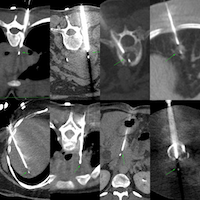

The patient came for a biopsy and I decided to use an anterior approach in the supine position.

I had described a splenic lesion biopsy earlier as Case 115.

Case 115: Splenic Lesion Biopsy

Splenic lesion biopsies are simple and straightforward. Bleeding and pain are the two main issues.